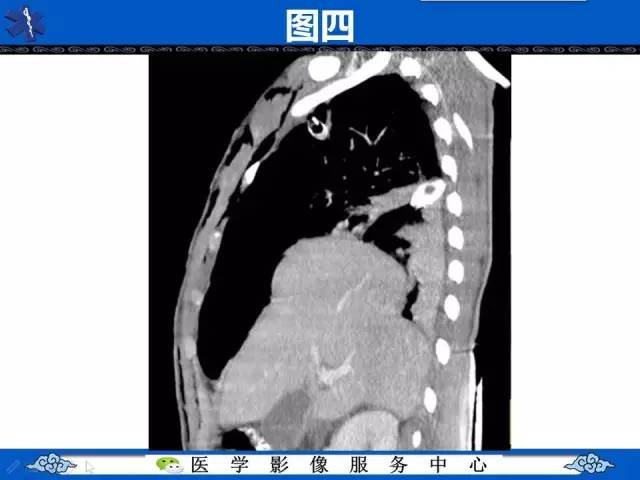

圆锥面包征——膈肌破裂

【影像征象】圆锥面包征——膈肌破裂